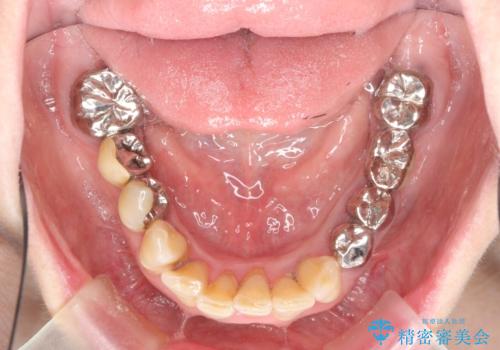

多発した虫歯による咬合崩壊 インプラントを用いた全顎治療

- 「これまで歯の治療をおざなりにしてしまい本当に後悔している。 時間と費用がかかってもいいので、しっかりと安心してかめるような状態にしてほしい。」、と全体的な治療を希望され来院されました。

歯の破折・再発した大きな虫歯・根尖病変・歯の欠損、これらの問題を根管治療・歯周外科・インプラント治療・セラミック補綴を行うことで一つづつ解決し安定した咬合状となるよう治療を進めます。